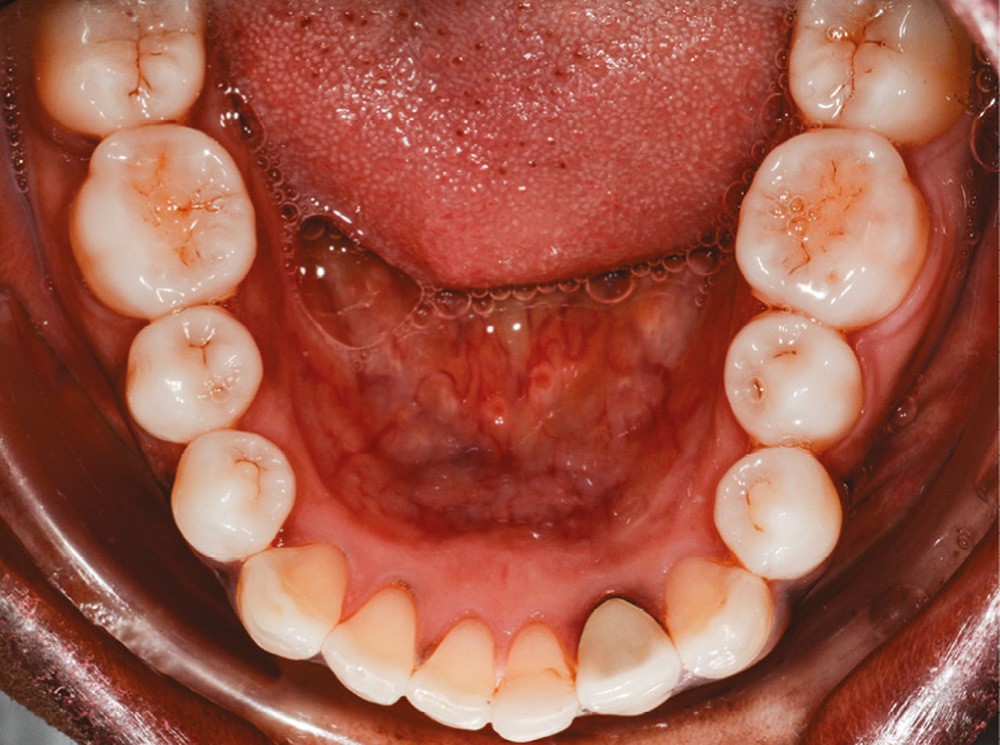

L’observation clinique après traitement parodontal initial révèle, au niveau interarcade, des rapports de classe I molaire bilatéraux associés à des rapports de bout à bout incisif. Dans la dimension verticale, elle présente une légère infraclusion antérieure. On ne note pas d’anomalie de la dimension transversale (fig. 3 à 5). À l’examen intra-arcade, on constate des diastèmes maxillaires interincisifs (1 mm), en distal de 13 (0,5 mm) et de 24 (1 mm) ainsi que des malpositions unitaires (linguoversion de 12, rotation mésio-vestibulaire disto-linguale de 24). À la mandibule, on observe une couronne céramométallique au niveau de 32 plus large de 1,5 mm que les autres incisives ainsi qu’une rotation mésio- linguale de 35 (fig. 6 à 8). En diduction, on note une interférence au niveau de 24.